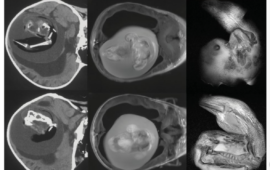

E’ successo in Cina, a Shanghai: un feto non ancora nato è stato rimosso dal cervello della gemella, una bambina di un anno. La bimba aveva la testa ingrossata e problemi motori: dopo una TC (tomografia computerizzata) i medici –